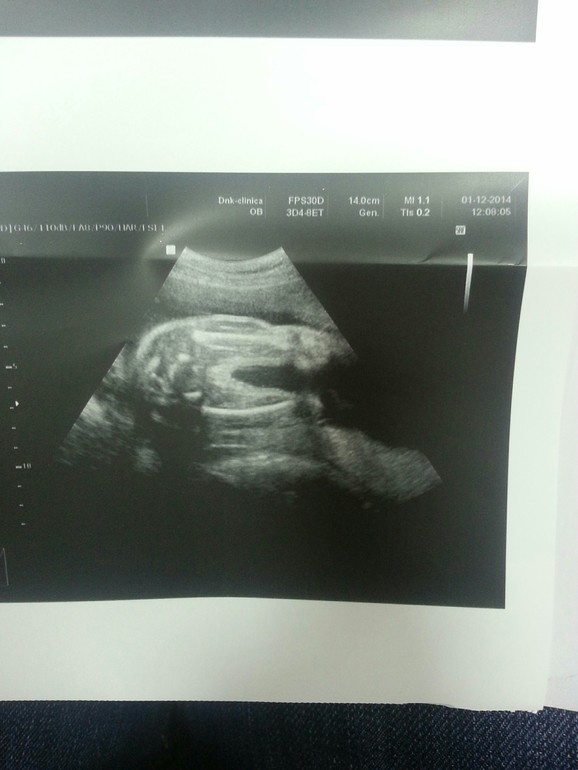

Пол малышаСходила на 4D узи. У нас будет. .. ДЕВОЧКАаааа)))

В 12 недель вообще не увидили. В 16 и 20 сказали на мальчика похоже (платно делала). А тут неделю назад в 24 сказали девочка, но не точно ( и в жк и платно). Ну а сегодня на 4D подтвердили девочку))) я так рада (хотя и сыну была бы рада. Я уже и ждала как то сына, обращалась к малышу как к мальчику). А тут бац и девонька))) ууииииии)))) папа наш очень рад)

Мы на попе сидим. Если смотреть на фото то это попа и ножки (вид снизу). Представьте что вы попой сели на сканер ))) ножки вправо направлены. Ну там типо как расхождение видите?)) И вот в этом расхождении и видно пол - девчушку)) у пацана бы там был писюнчик)) посмотрите в инете фото узи мальчиков и девочек.